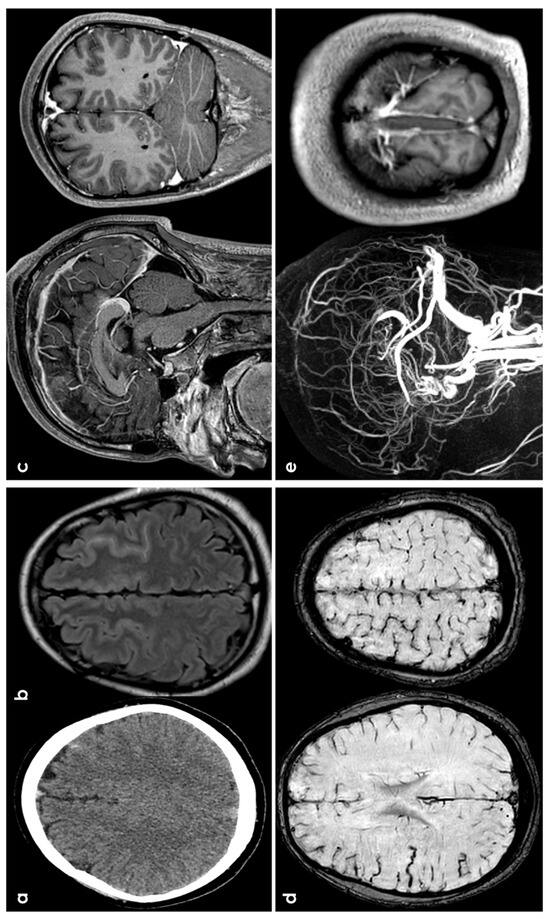

3.1. CAA

3.2. Hemodynamic Arterial Stenosis

3.3. Infective Endocarditis

3.4. Cerebral Venous Thrombosis